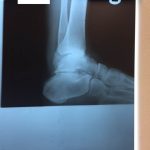

Ten years of severe ankle pain with a mal-positioned ankle fusion is now relieved! Patient is now walking with pain-free ankle motion!